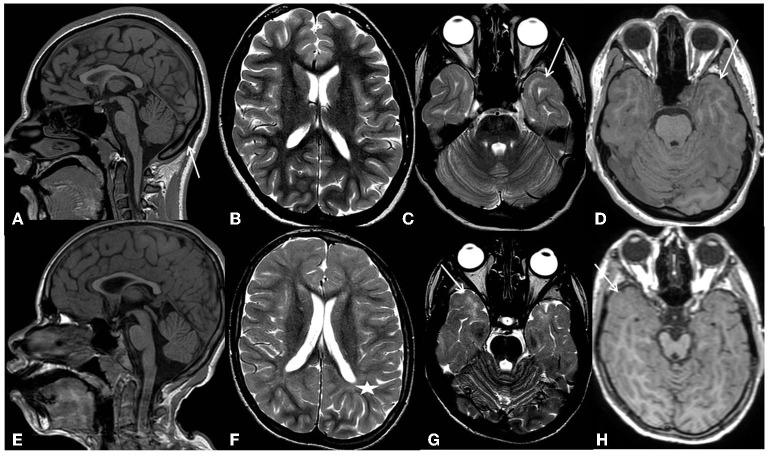

病例报告:具有变异的儿童神经学特征中的早发性帕金森病

Case report: Early-onset parkinsonism among the neurological features in children with variants.

is expressed in cardiovascular and neurological tissues. In the brain, it has a role in pre- and post-natal maturation. Previously reported -mutated patients showed early-onset epilepsy and intellectual disability. We describe two unreported cases with pathogenic variants in and their clinical pictures, compared with those of cases already reported in the literature. In line with previous reports, the two patients presented early-onset developmental and epileptic encephalopathy. In addition, one patient developed a speech disorder and a progressive movement disorder characterized by hypertonus, hypo-bradykinesia, hypomimia, ataxic gait, and retropulsion. She was treated with levodopa without any clinical improvement. Pathogenic variants in may result in a cardiological or neurological phenotype. Severe developmental delay, intellectual disability, and early-onset developmental and epileptic encephalopathy are the main features of -mutated patients with neurological involvement. Movement and speech disorders have never previously been described and could be new features of the neurological phenotype.

摘要

在心血管和神经组织中表达。在大脑中,它在产前和产后成熟过程中发挥作用。先前报道的突变患者表现出早发性癫痫和智力残疾。我们描述了两例未报道的携带致病变体的病例及其临床症状,并与文献中已报道的病例进行了比较。与先前的报道一致,这两名患者均出现早发性发育性和癫痫性脑病。此外,一名患者出现了言语障碍和进行性运动障碍,其特征为肌张力亢进、运动徐缓、表情减少、共济失调步态和后冲。她接受了左旋多巴治疗,但没有任何临床改善。致病变体可能导致心脏或神经表型。严重发育迟缓、智力残疾以及早发性发育性和癫痫性脑病是携带突变且有神经受累的患者的主要特征。运动和言语障碍以前从未被描述过,可能是神经表型的新特征。